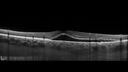

44 year old white female: She noticed vision problem in the left eye for 3 weeks. Since it started it is not getting any better. She has been on flonase for less than a year. She is also on systemic prednisone 5 mg per day. This started October 21st with a lupus flare initially with 10 mg and then down to 5 mg. She has, in the past, taken systemic steroids, 35 mg, for autoimmune hepatitis. At that time she had no problem with her vision. She was initially seen for plaquenil screen and was fine about a month before the vision got worse.

Meds: Plaquenil, Cellcept, Flonase, Ursodiol

VA OD: sc20/20 NscJ1+VA OS: sc20/25 NscJ2